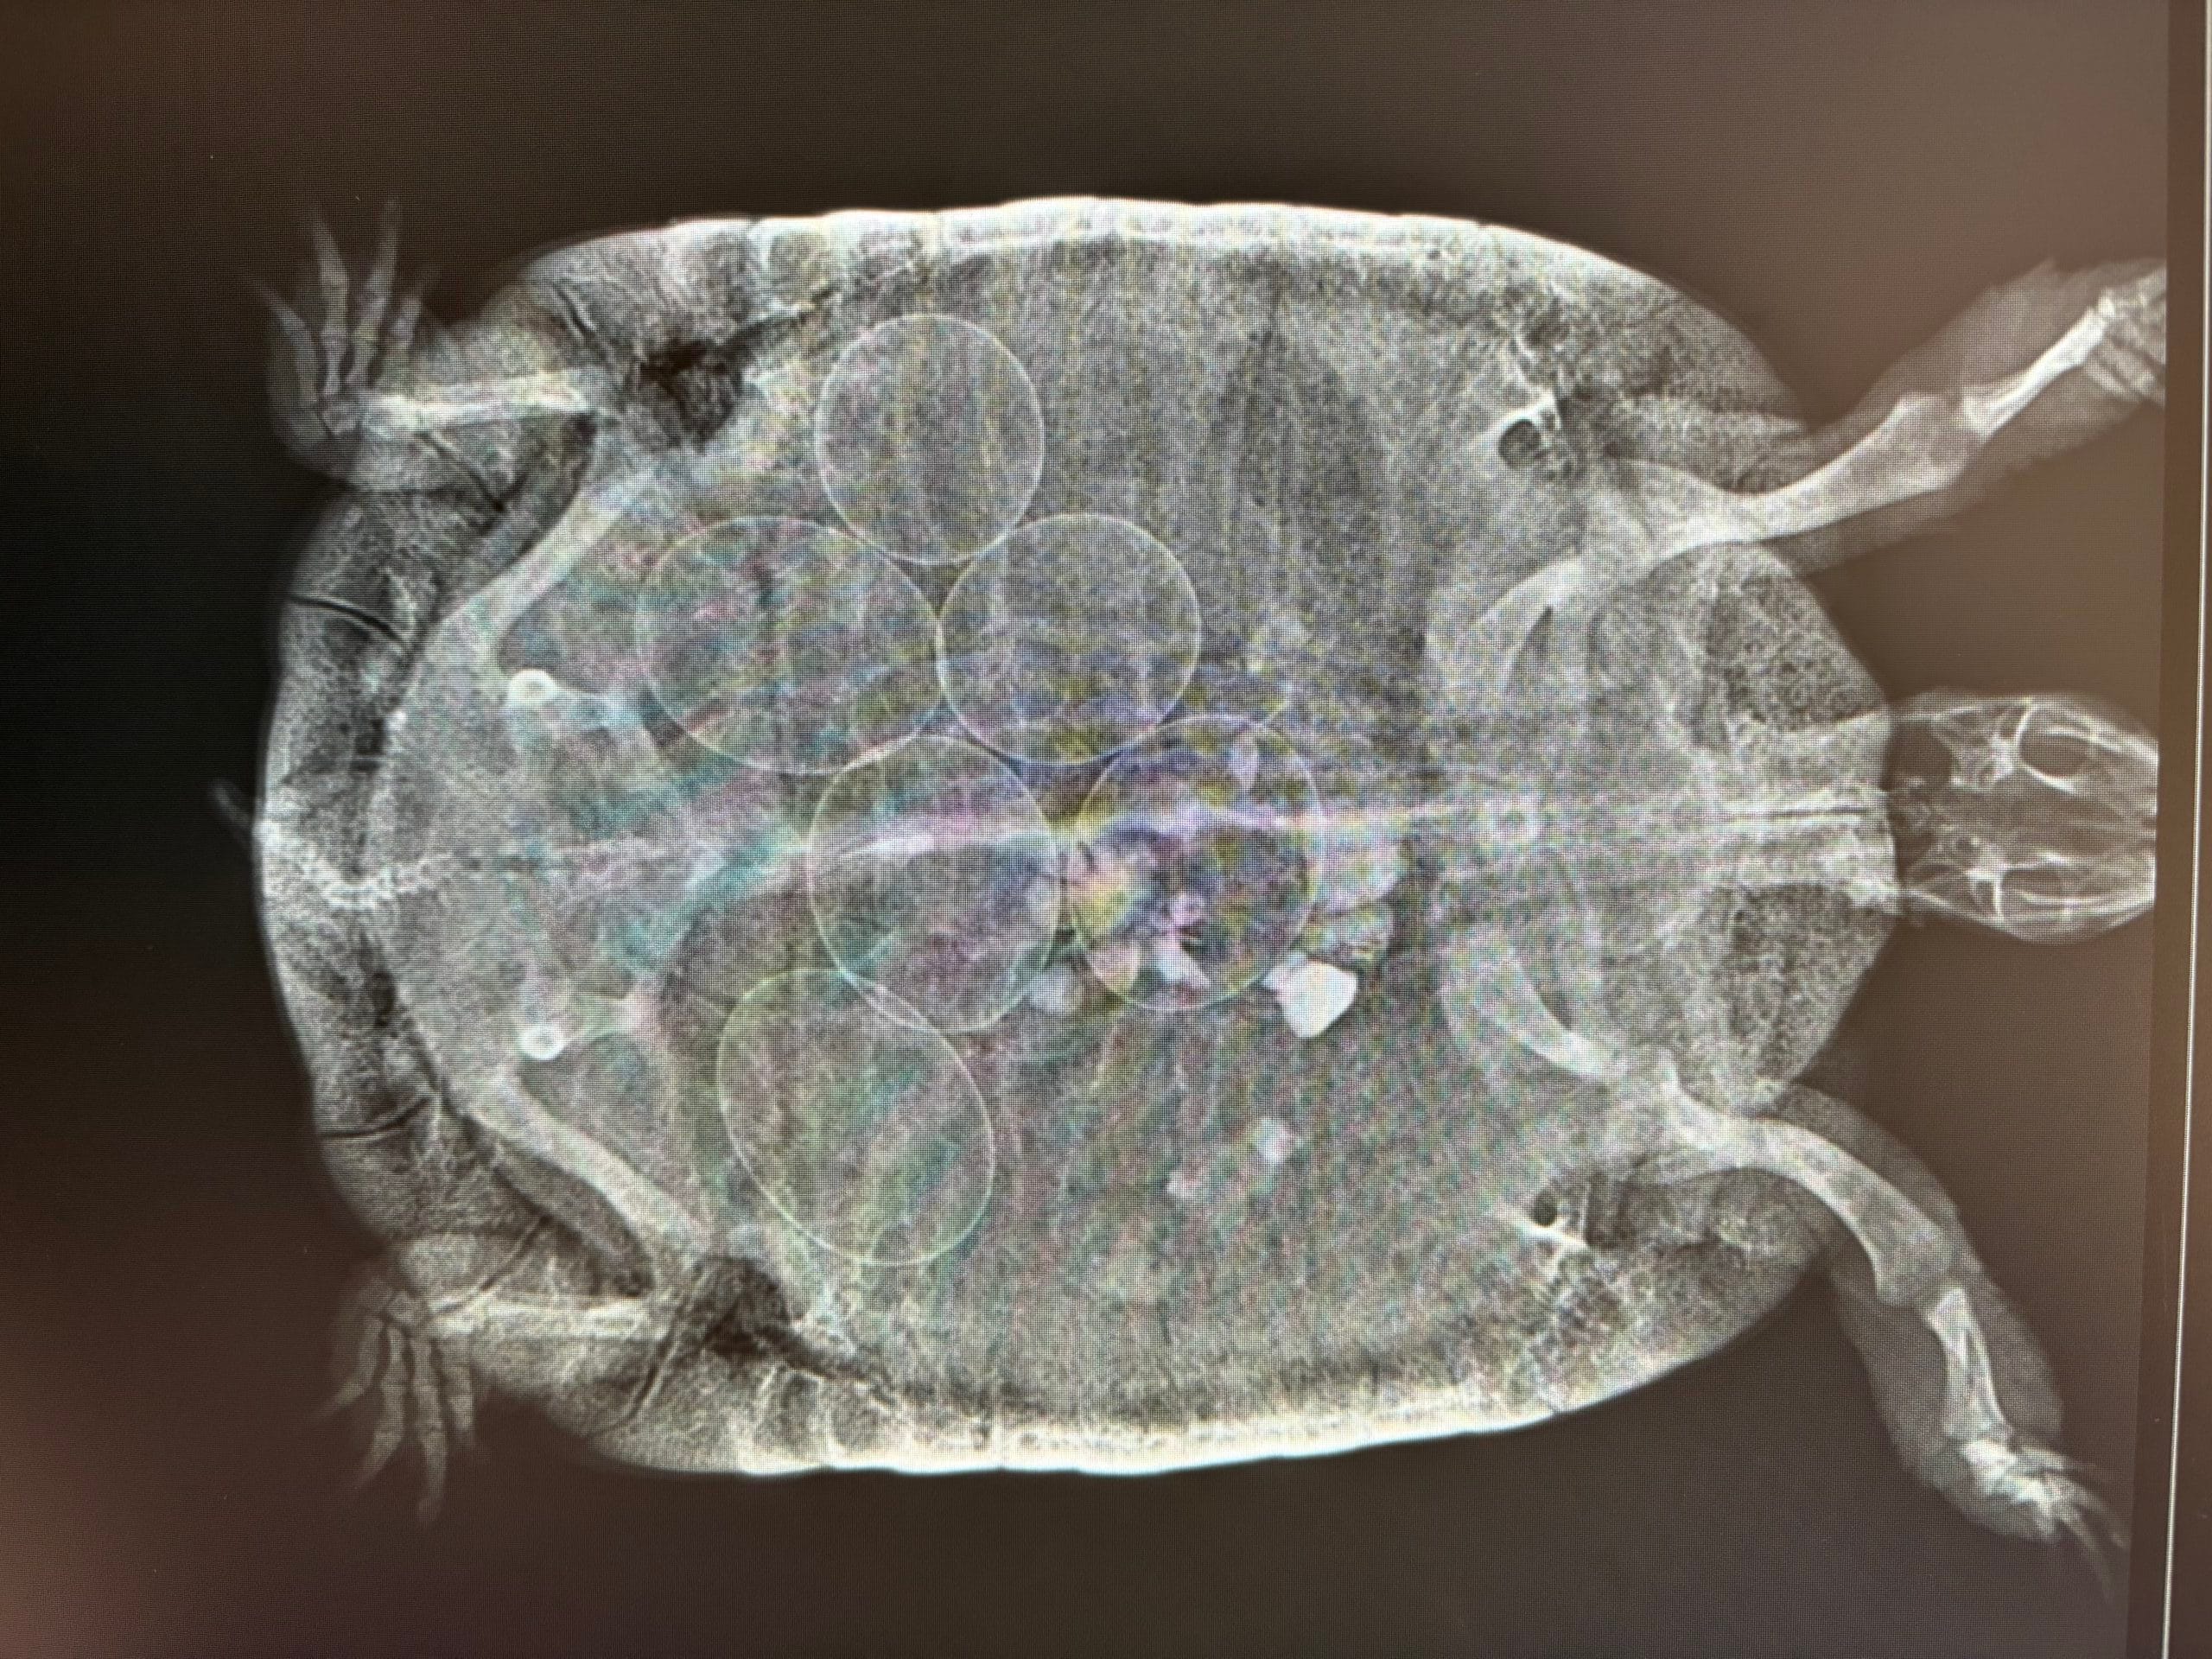

Un aumento di volume degli organi interni nelle testuggini può provocare schiacciamento del nervo sciatico che comporta dolore alla deambulazione del treno posteriore. Se siamo di fronte ad una femmina adulta (sopra i 10 anni) nella stagione tipica dell’ovodeposizione (tra aprile-maggio e tra luglio-agosto) dobbiamo sospettare la presenza di un’elevata quantità di uova nel celoma. La cosa da fare è sempre portarla da un veterinario esperto in esotici, nello specifico di rettili, ed effettuare una radiografia per verificare la presenza o meno delle uova. È importante ricordare che la presenza di uova in radiografia non indica automaticamente una distocia: solo una valutazione clinica completa può stabilirlo.